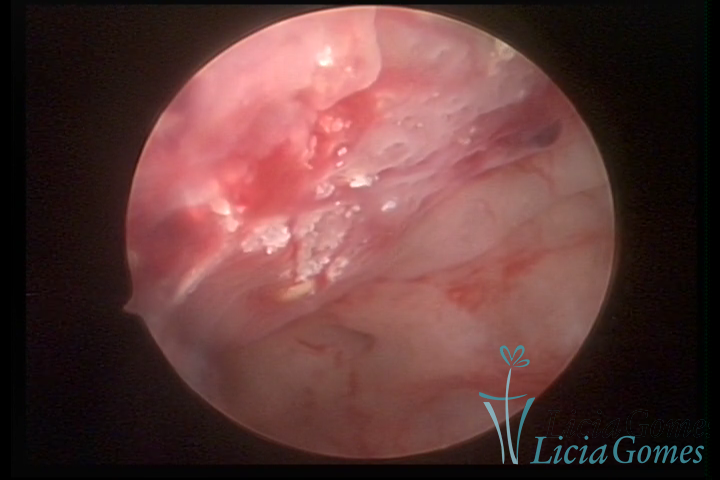

Osseous metaplasia: white spots with calcifications